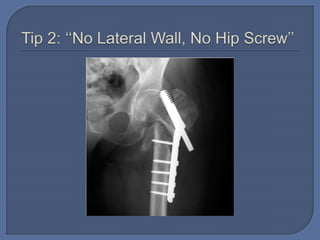

 Tip 2: ‘‘No Lateral Wall, No Hip Screw’’

 Tip 2: ‘‘No Lateral Wall,

No Hip Screw’’

 Planning: • Nailor Screw? • Nail or screw properties  Execution: • Open • Reduce • Fix • Close  Tip 2: ‘‘No Lateral Wall, No Hip Screw’’  Tip 3: Know the Unstable Intertrochanteric Fracture Patterns, and Nail Them